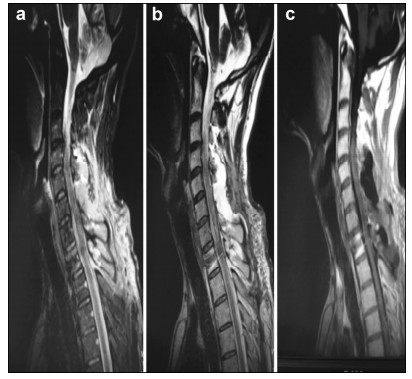

A 46-year-old male presented with a 4-year history of upper and lower limb numbness and weakness (motor strength 4/5 and 2/5 in upper and lower limbs, respectively). Symptoms worsened 30 days before consulting our facility. Magnetic resonance imaging (MRI) of the spinal cord showed an intramedullary mass at C5-C6. Surgical resection under awake anesthesia was recommended; the patient received detailed information regarding the procedure and possible risks, and informed consent was obtained. He remained intubated and his motor speech function was not monitored, because the language center was not involved in surgery. The patient followed commands and performed all upper and lower limb movements as instructed. Sensory functions were not fully assessed; instead, minimal monitoring was performed with sensory stimulation of his hands and feet, with instruction to raise his thumb if he perceived sensation. GTR of the tumor was performed under awake (AAA) anesthesia with neurophysiological monitoring (NPM). Intraoperative frozen section confirmed the diagnosis of diffuse spinal cord astrocytoma. Symptoms completely resolved postoperatively, and no motor deficits were observed; however, there was minimal numbness in the finger tips.

Preoperative and postoperative MR images of Case 1 are shown in Figure 1 and Figure 2, respectively.

| Figure 2 a–c. Postoperative MR images of Case 1 |